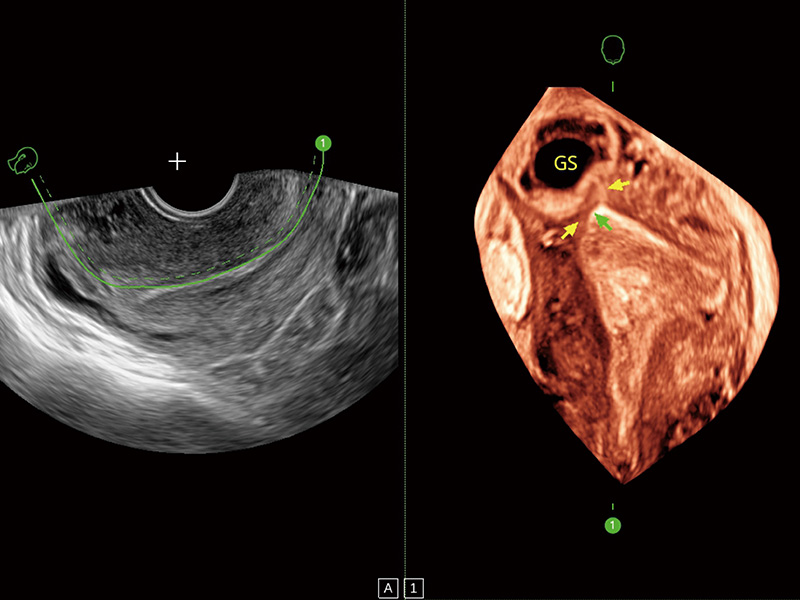

腔内容积探头

腔内三维成像技术获得显著提升,超大扇角在满足日常基础扫查的同时,支持卵泡自动测量及多种三维渲染模式,为您提供更多的诊断信息,尤其是在子宫畸形的诊断,内膜及肿瘤占位观测中起到了重要的作用。

超声引导下胚胎移植